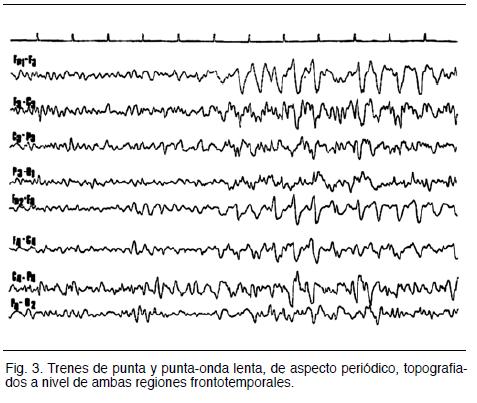

La electroencefalografía es una herramienta diagnóstica importante; no existen de hecho EEG normales. La EEG muestra elementos de enlentecimiento que suelen ser focales, luego aparecen complejos trifásicos característicos con dominancia temporal (figura3). Algunos pacientes desarrollan descargas epileptiformes periódicas lateralizadas (PLEDs) a un ritmo de 1-5 Hz, que se originan en el lóbulo temporal, que son altamente sugerentes de EH, aunque no patognomónicos. Su ausencia no invalida el diagnóstico; pueden estar ausentes al inicio, y la resolución de estas anomalías no se correlaciona bien con la clínica (8,17).